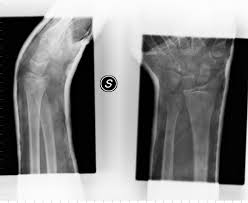

Intervento chirurgico

Osteotomia intraarticolare del frammento viziosamente consolidato e osteosintesi con placca volare in acciaio Precise SVP.

Fase 1: osteotomia e stabilizzazione provvisoria con fili di Kirschner

Controllo intraoperatorio con amplificatore di brillanza

Fase 2: il frammento volare viene fissato solo con 3 viti bloccate.

Il supporto sub condrale e la tenuta delle viti permettono di affidarsi a un numero di viti limitato sufficienti a garan-tire la tenuta del frammento osseo.

Decorso post-operatorio

Mobilizzazione precoce dopo 2 settimane, che ha permesso un buon risultato funzionale a 2 mesi dall’intervento.

Controllo radio grafico finale